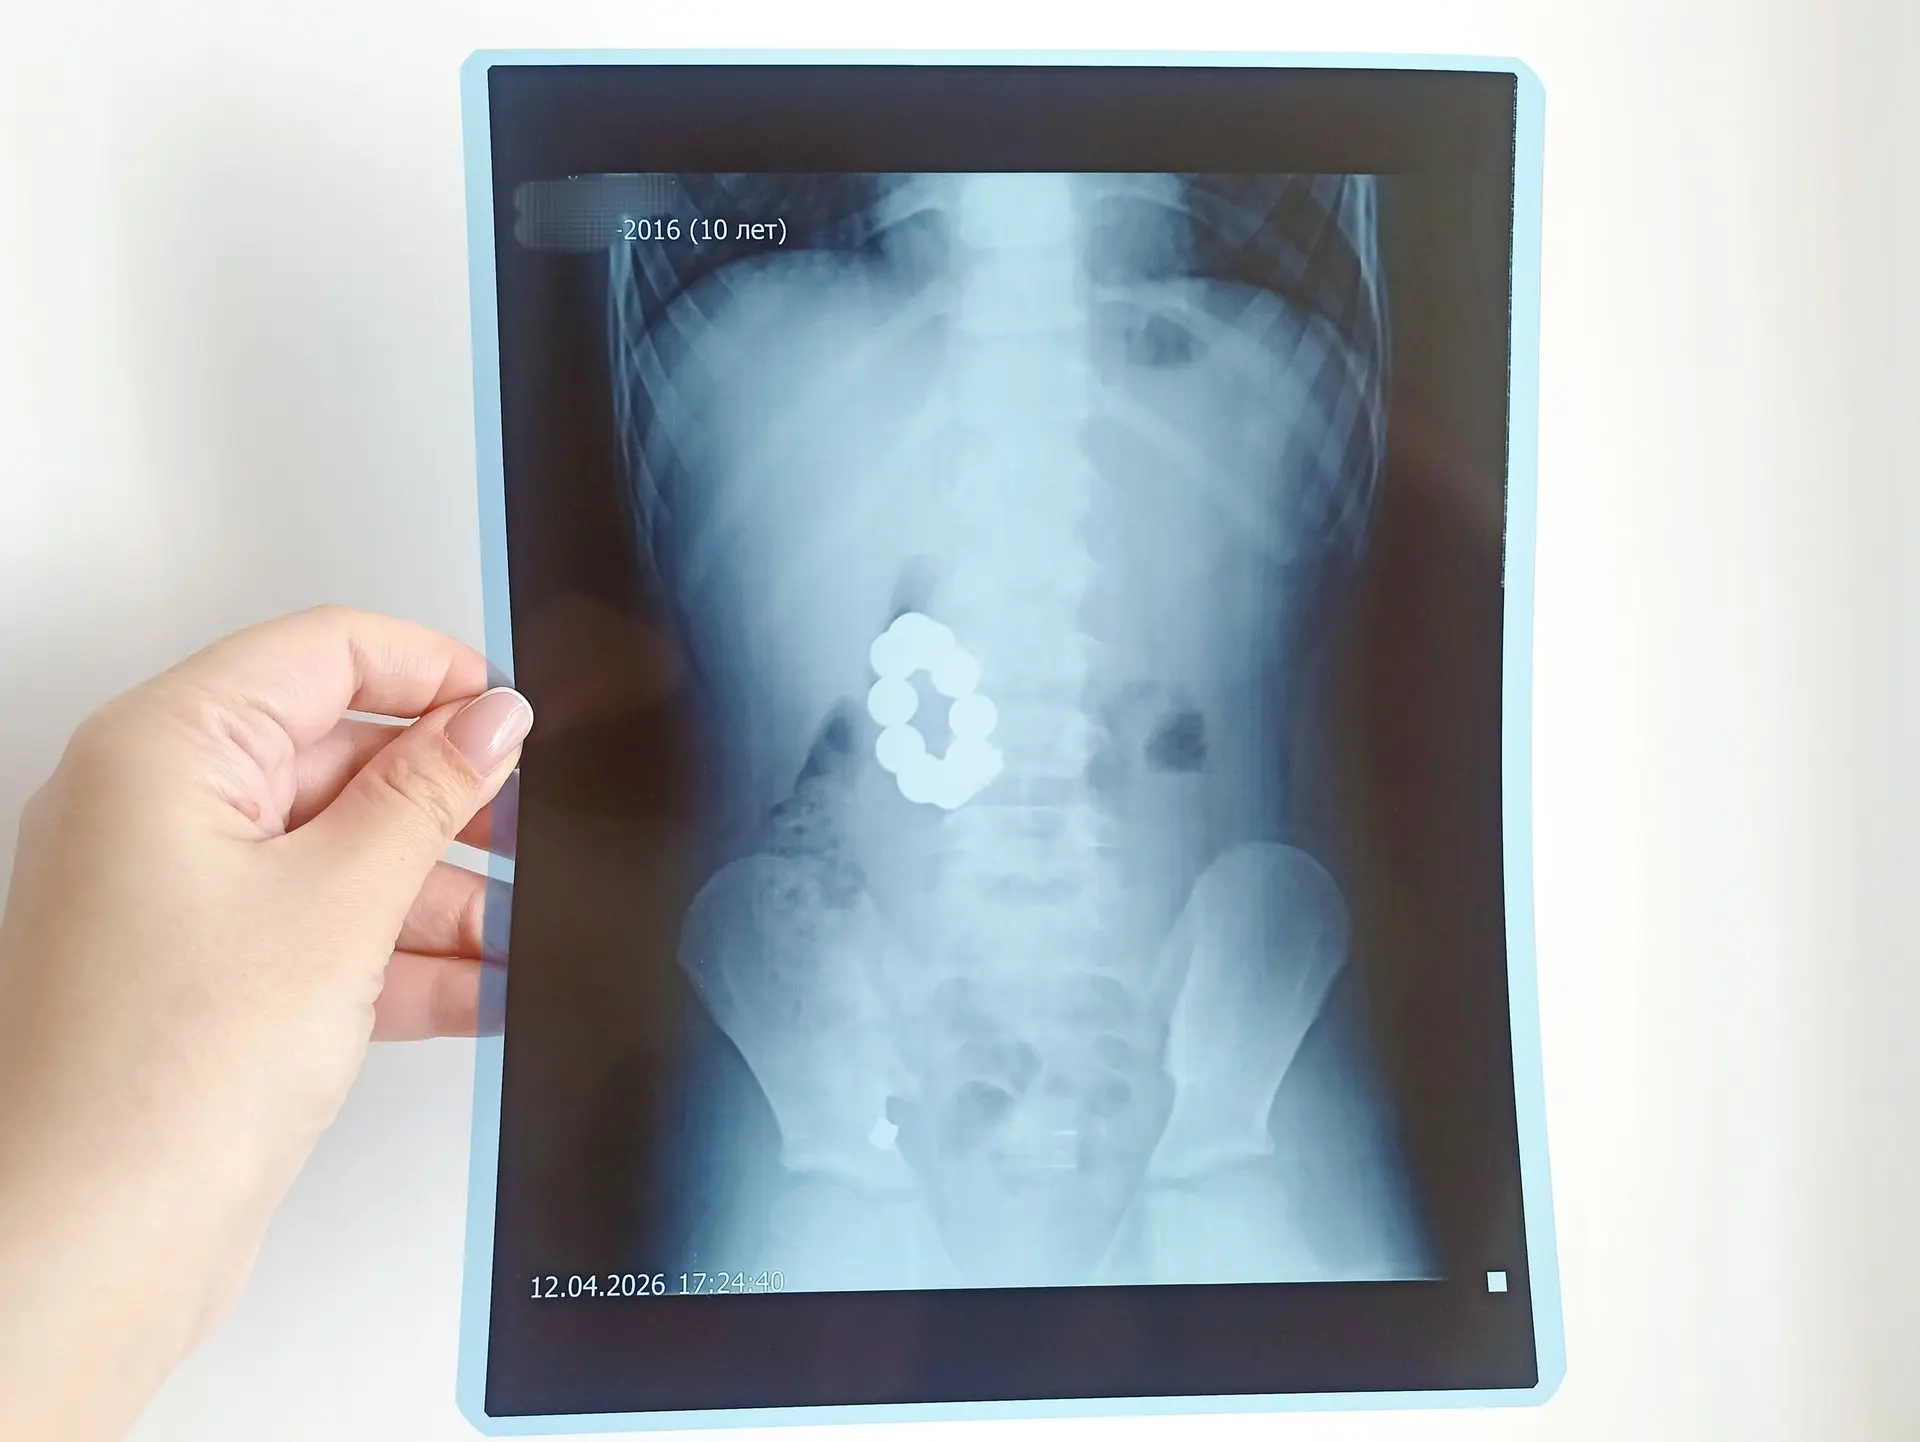

10-летний мальчик из Крутихинского района настолько увлекся игрой с магнитными шариками, что решил проглотить манящие предметы. Через пару дней с болью в животе и рвотой его доставили в больницу в Камне-на-Оби.

Оттуда пациента направили в Детскую городскую клиническую больницу №7 Барнаула. Рентген показал, что предметы — 10 сантиметровых магнитов — сцепились между желудком и двенадцатиперстной кишкой. Помимо шариков медики обнаружили еще одно инородное тело — металлическую цепочку от брелока.

«Поставив диагноз, мы сразу решили, что пойдём на лапаротомию — открытую операцию, не будем терять время на проколы. Произвели гастротомию — рассечение желудка. Сначала удалось извлечь шесть шариков и цепочку. Остальные магниты, которые находились в двенадцатиперстной кишке, достаточно долго подводили к разрезу. Их удалось достать с помощью зажимов», — вспоминает заведующая детским отделением гнойной хирургии ДКГБ №7 Нина Мамонтова.